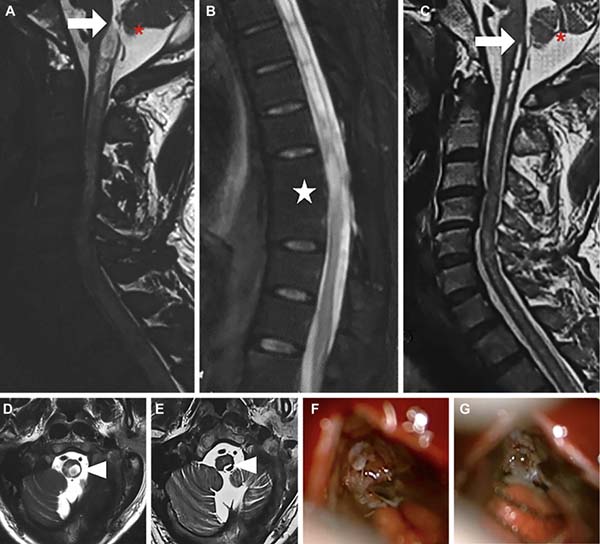

4*岁男性,左颈肩痛伴上肢痛1年。既往9年前胸髓损伤史。术前MRI(图A-B、D)显示患者存在颈胸段脊髓空洞及延髓空洞,T8水平可见腹侧局部粘连。 FMMD手术后复查MRI(图C-E)显示空洞明显缩小,患者症状得到显著改善。术中影像(图F-G)证实Magendie孔存在明显阻塞,并经手术成功疏通。

图4 胸椎脊髓损伤后继发空洞延伸到延髓典型病例示意图